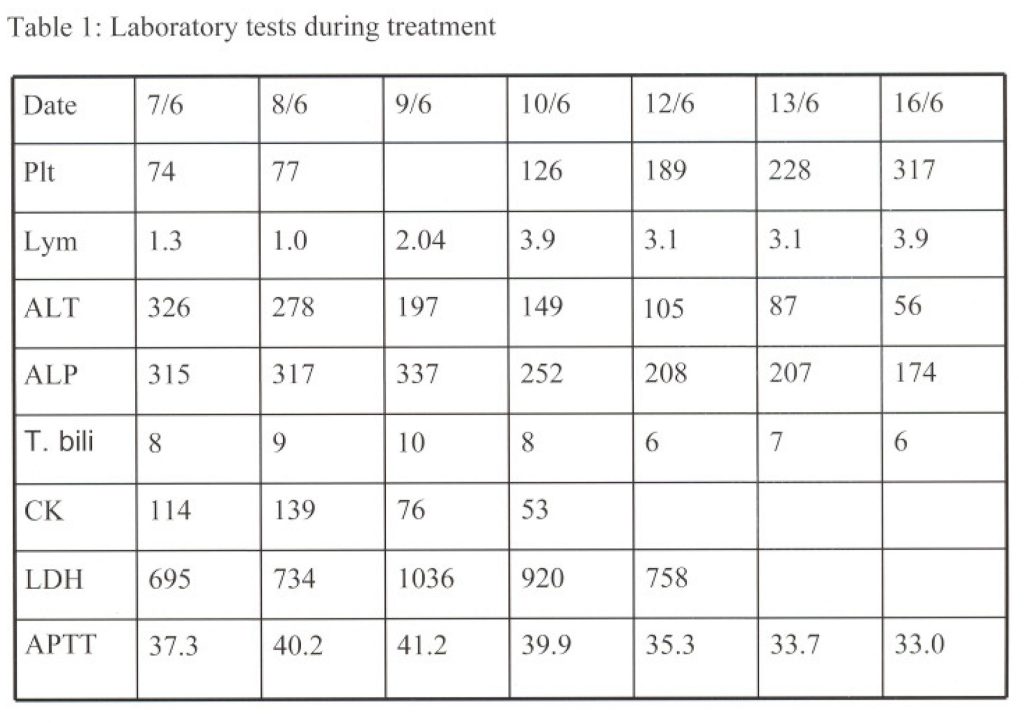

The working diagnosis was therefore changed from suspected SARS to typhus based on the clinical features. Anti-retroviral drugs and steroid were not given eventually. Doxycycline 100mg was given orally at once and continued with intravenous levofloxacin. Her symptoms improved substantially, so were her CXR (Figure 5), biochemical and haematological pictures (Table 1).

The Weil-Felix agglutination test only showed mildly raised OX 19 titre at 40, while both OX K and OX 2 titres were not raised at 20. Her Widal test was negative. The IgM antibody for dengue virus was negative. The IgG-CoV titre, and stool, nasal and throat swabs for SARS CoV RT-PCR repeated on 13 June 2003 were 40 and negative, respectively. The specific rickettsial serology by immunofluorescent method later confirmed she had scrub typhus with titre of 640. Other rickettsial group titre were not raised: spotted fever group < 80, typhus group < 80 and R. coroni < 80. Her fever came down since 10 June 2003 and clinical symptoms subsided substantially. She was discharged with resolution of biochemical, haematological and radiological abnormalities.